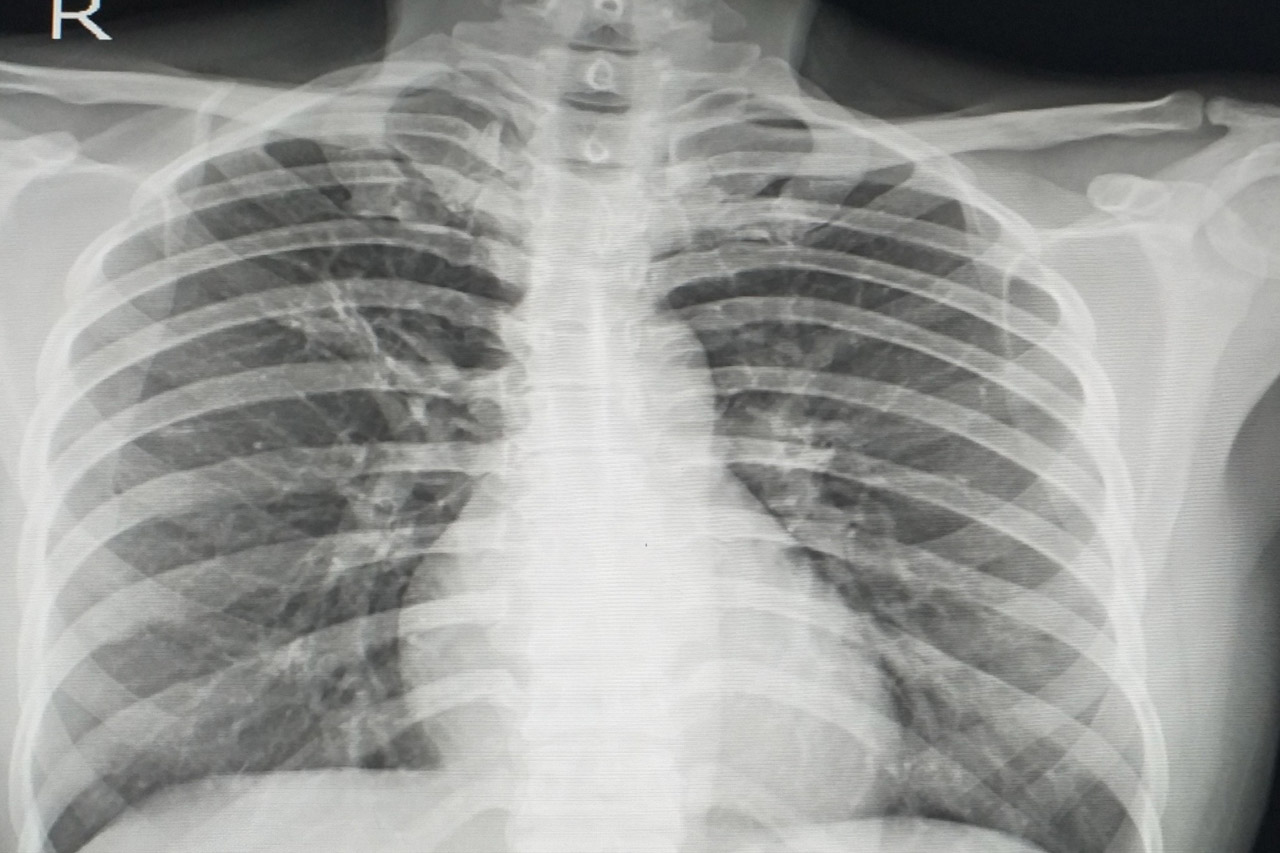

Рентгеновские технологии: усиленные экраны 35x35

Раздел: Фотопутеводитель